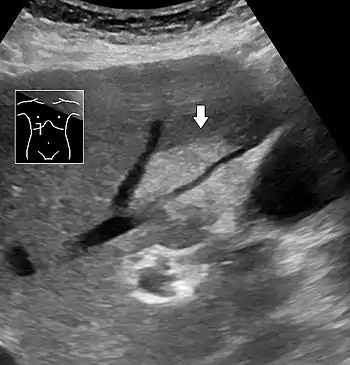

Medical imaging

On X-ray computed tomography (CT), the increased fat component will decrease the density of the liver tissue, making the image less bright. Typically the density of the spleen and liver are roughly equivalent. In steatosis, there is a difference between the density and brightness of the two organs, with the liver appearing darker.[11] On ultrasound, fat is more echogenic (capable of reflecting sound waves). The combination of liver steatosis being dark on CT and bright on ultrasound is sometimes known as the flip flop sign.

On abdominal ultrasonography, steatosis is seen as a hyperechoic liver as compared to the normal kidney.